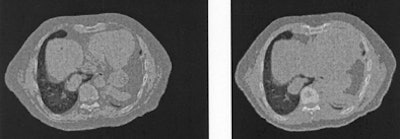

| On the left is one slice of the initial source CT. On the right is the same slice portraying the anatomy at a later time, reconstructed by deforming the source slice, making a synthetic sinogram projection through it, and matching that projection to the sinogram corresponding to the later CT slice. All images courtesy of Michael Murphy, Ph.D. |

First a 2D voxel-by-voxel displacement field was created and applied to the source slice to simulate the later CT. From the deformed target image, 1,500 projections were made and stored to represent the newly acquired target projection data, and the B-spline model was applied to create deformed source images. The gradient-driven iteration sequence was then used to update the deformation model.